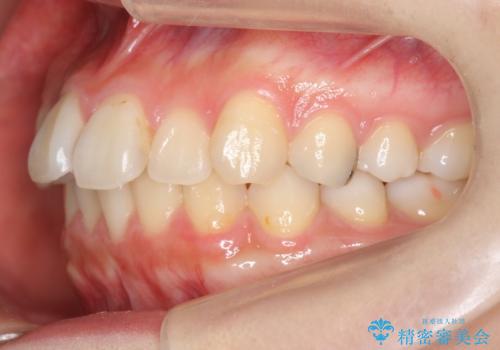

軽度の前歯のがたつき 下の前歯が生まれつき少ない

- 前歯のがたつきを主訴に来院。

下の前歯が生まれつき3本でした。

そのため、上の前歯が少し余るような形で出っ歯になっていたため、スペースを作って引っ込めています。

下を3本でそのまま並べてあるため、上下の正中は合いません。

合わせようとすると抜歯か、下の隙間を無理やり開けてブリッジとなりますが、そこまでするメリットがないため、下はそのままの歯の数を生かしています。